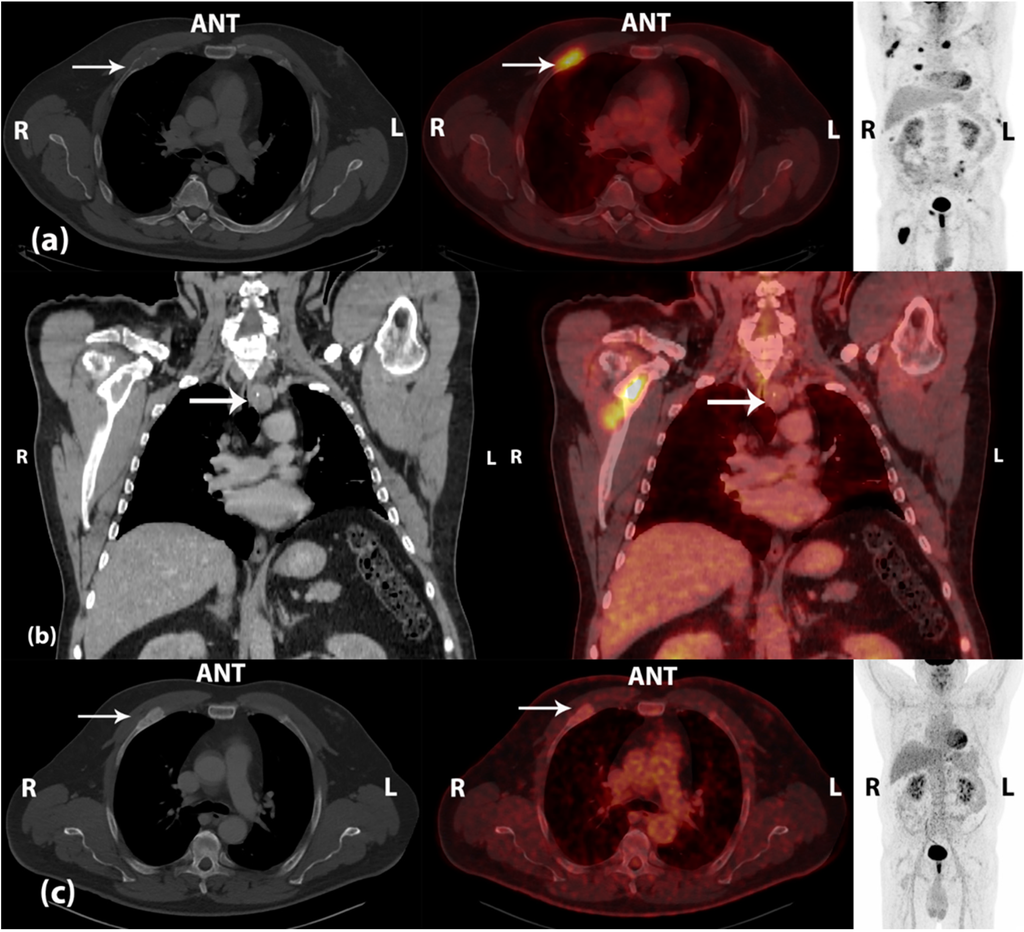

Brown Tumors Due to Primary Hyperparathyroidism in a Patient with Parathyroid Carcinoma Mimicking Skeletal Metastases on 18F-FDG PET/CT